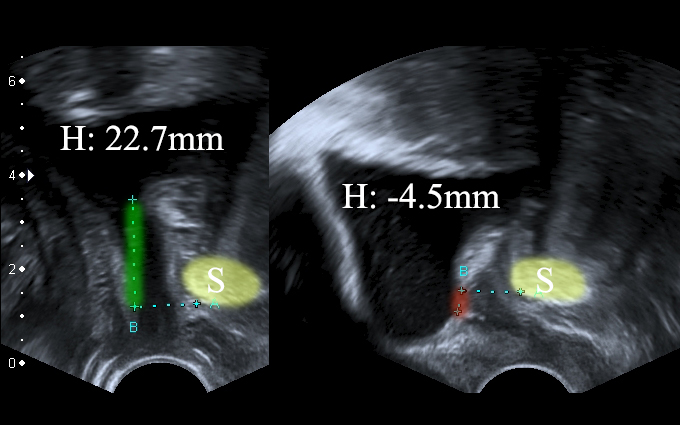

Significant bladder neck descent (ΔH: 27.2mm). Left: patient is relaxed. Right: patient performs Valsalva.